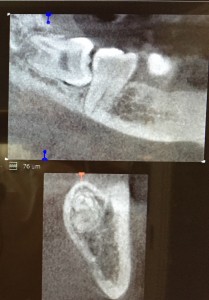

親知らずは横向きに生えていると、手前の歯にぶつかって、それ以上出てきません。

半分ぐらい歯茎の外に出ている場合は、どうしても手前の歯との間に汚れがたまり、そこから手前の歯を含めて虫歯になったり、歯周病が進んだりします👿

親知らずの手前の歯は、一生必要ですので、症状を繰り返しながら段々と悪くなるのを待つよりは、原因となる親知らずを抜歯する事が望ましいです。